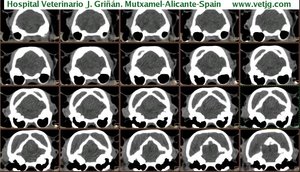

imágenes de TC en el gato | |||||||||||

Mismo paciente: Correspondencias entre el corte sagital y el volumen, ambos reconstruidos a partir de imágenes TC (transversales) |

Tomografía computarizada helicoidal |